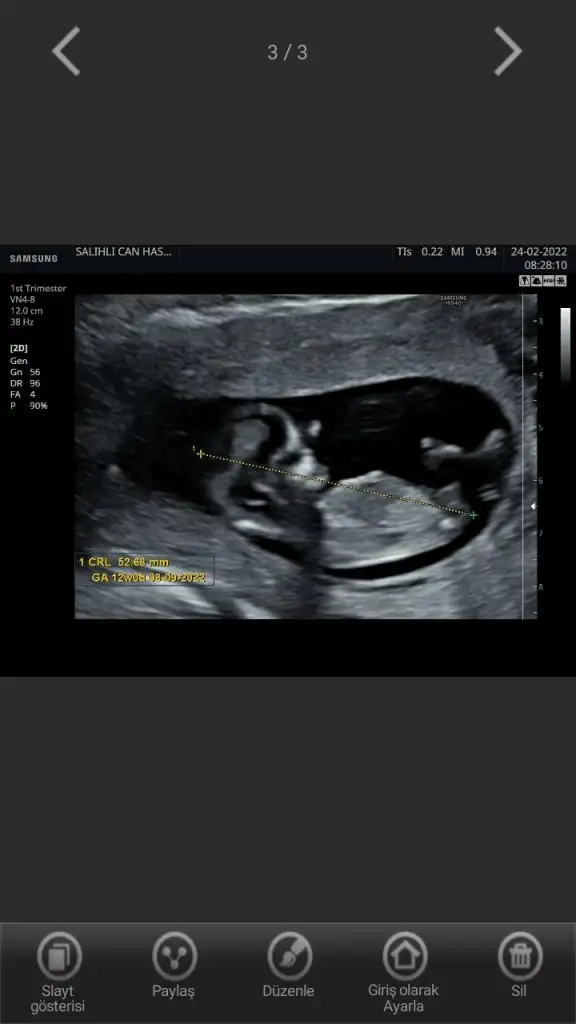

Kontrolden döndük kızlar. Şükür her şey yolunda, 3 gün öne bile geçmişiz. Bugün ikili test ölçümleri yapıldı, ilk denemede o kadar hareketliydi ki görüntü alamadık, ikinci deneme başarılıydıCinsiyet konusunu bir sonraki kontrolde netleştirebiliriz dedi. Sizin tahminlerinizi alabiliriz

%70 kız diyorumKontrolden döndük kızlar. Şükür her şey yolunda, 3 gün öne bile geçmişiz. Bugün ikili test ölçümleri yapıldı, ilk denemede o kadar hareketliydi ki görüntü alamadık, ikinci deneme başarılıydıCinsiyet konusunu bir sonraki kontrolde netleştirebiliriz dedi. Sizin tahminlerinizi alabiliriz

Oy maşallahKontrolden döndük kızlar. Şükür her şey yolunda, 3 gün öne bile geçmişiz. Bugün ikili test ölçümleri yapıldı, ilk denemede o kadar hareketliydi ki görüntü alamadık, ikinci deneme başarılıydıCinsiyet konusunu bir sonraki kontrolde netleştirebiliriz dedi. Sizin tahminlerinizi alabiliriz

Kızlar benim de kontrolüm güzel geçti şükürler olsun her şey yolunda 11+3 ama tam 12 çıktı bugün. İkili testi sordum, doktorum izah etti biraz düşüneceğim dedim. Bakalım biraz araştırıp eşimle konuşup karar vermemiz lazım.